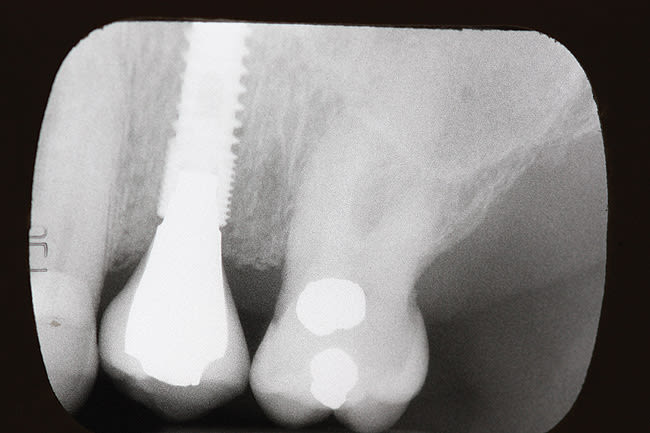

A 4.3-mm diameter Hiossen implant (www.hiossen.com) was placed and maximum torque of 60 newton centimeters was achieved. The implant used in this case had microthreads on the top quarter of the implant and the abutments placed were narrower than the head of the implant. This relationship of decreased abutment/implant diameter is described as platform switching. The implant was fully integrated and uncovered in 4 months, with a temporary abutment placed (Figure 2). With an internal connection design—which can create an optimal condition for the preservation of crestal bone—providing a more rigid connection from a mechanical standpoint,10 the implant was restored using a traditional PFM crown, which established optimal emergence profile. Figure 3 shows the crown in place for 18 months, with no tissue inflammation.

In a similar case, a 45-year-old man presented with tooth No. 13 fractured 2 years after having a porcelain crown made (Figure 4). His dental condition was excellent with only five amalgam fillings in his mouth. He was interested in an immediate replacement because he felt uncomfortable chewing without this tooth. He had considered a fixed bridge but was reluctant to prepare the two adjacent teeth, which had very small amalgams in them. He elected to have the root extracted and an immediate implant placed. Figure 5 is an x-ray of a 4.3-mm Hiossen implant placed with a torque of 60 newton centimeters and restored with a provisional abutment. After the patient felt the bite was comfortable, a final crown with a screw-retained single-piece crown and abutment (Figure 6) was inserted. The x-ray pictured is 2 years post-insertion with no bone loss visible. The implant has maintained the same alveolar bone level since placement and appears stable due to the platform-switch placement of the abutment.